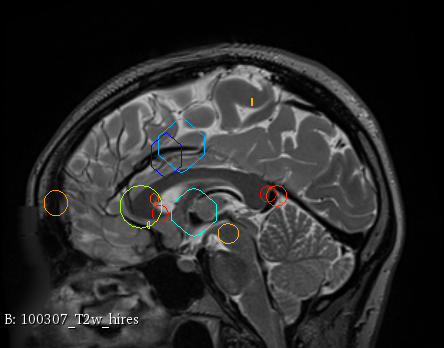

Figure 3 provides a scale-space visualization of feature matches for a single pair of MZ twins and NT siblings, where scale information is represented using the circle radius. Note that circles represent the intersection of 3D spheres with the visible slice and, thus, non-intersecting features are hidden in this 2D visualization.

It can be seen that different image modalities generally result in distinct, complementary feature correspondences throughout the brain, allowing a rich characterization of both anatomical and connectivity structure. In T1 and T2 images, features are mainly located in the frontal lobe, corpus callosum and brain stem. Smaller-scale features are also visible along various cortical regions, as well as in sub-cortical structures near the basal ganglia. Although highly correlated, T1 images show significantly more feature matches than T2 images. Moreover, images based on diffusion measures have less matches than in structural modalities. These matches are located mostly inside or near to white matter: larger-scale features in the corpus-callosum, and smaller-scale ones in the brain stem and along white matter bundles. While not shown in the figure, the set of matches found by combining two modalities (e.g., T1 + T2) generally corresponds to the union of those obtained with these individual modalities.

Comparing different sibling types, we observe a greater number of matches between MZ twins than NT siblings. This observation, which is easier to visualize in T2 and GFA images, is consistent with other analyses on twin datasets. In terms of feature location and scale, no obvious pattern can be seen when comparing these two sibling types. However, a more detailed analysis would be required to validate this assertion.